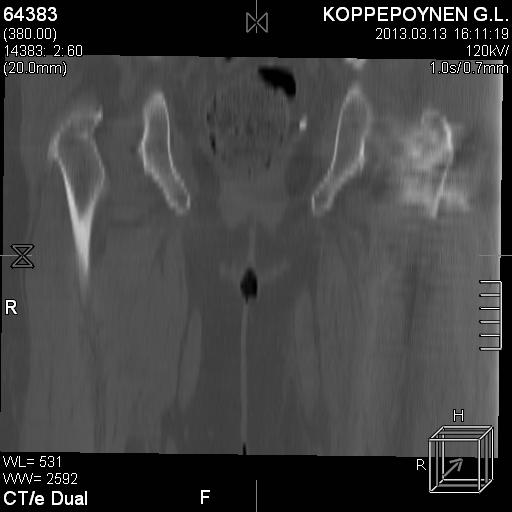

[Ortho] Чрезподвертельный перелом бедра. Остеосинтез стержнем. Перелом металлофиксатора. Дальнейшая тактика?

Делали КТ после операции.